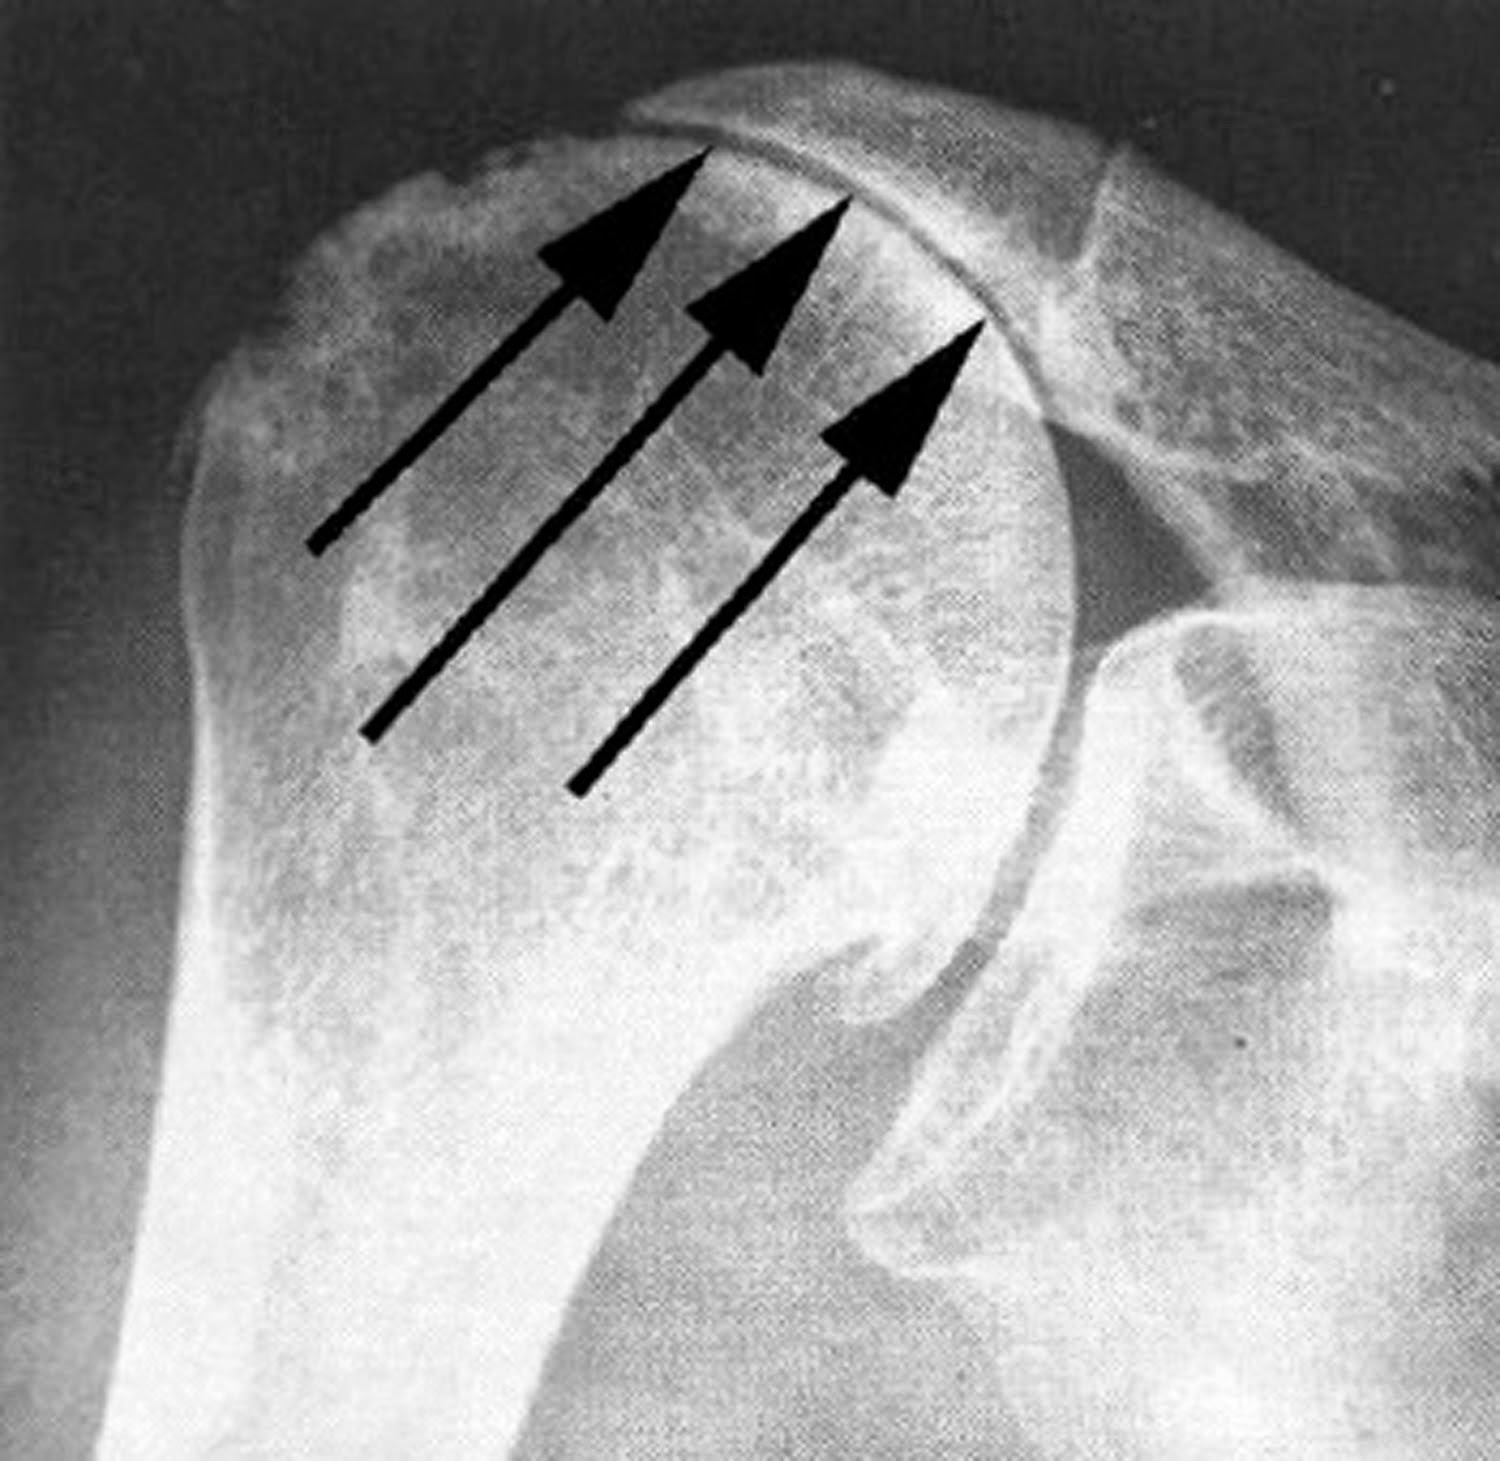

Rotator Cuff Arthropathy Shoulder & Elbow Orthobullets Arthritis In Shoulder Rotator Cuff Pain from a problem with the rotator cuff is. the most frequently occurring types of arthritis which affects the shoulder are osteoarthritis, inflammatory arthritis, rotator cuff tear. the rotator cuff is a group of muscles and tendons that keep the upper arm bone held in the shoulder blade socket. rotator cuff tear arthropathy (or shoulder arthritis with. Arthritis In Shoulder Rotator Cuff.